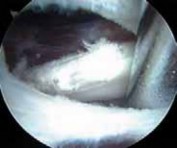

TECHNIQUES A B C D E F G H I ### FIG 4 • A–G. The iliopsoas tendon of the right hip is exposed from the peripheral compartment. A. The initial tendon viewed through a capsular window is fully identified, but is abnormally small. B. This tendon is released with a basket. C. A stump remains. D. This is resected with a shaver. E. Further dissection exposes a more substantial portion of the iliopsoas tendon. F. This is released as well. G. Complete release of the bifid tendon is documented. H,I. Viewing the iliopsoas tendon of a right hip at its insertion on the lesser trochanter within the iliopsoas bursa. H. A bifid iliopsoas tendon is identified with medial (

) and lateral () bands separated by a vessel (

two white asterisks

) coursing perpendicular. I. The lateral band (

black asterisks

) has been released with a flexible RF device, revealing the medial band (

white asterisk

) which subsequently is released. (Courtesy of J. W. Thomas Byrd, MD.)**